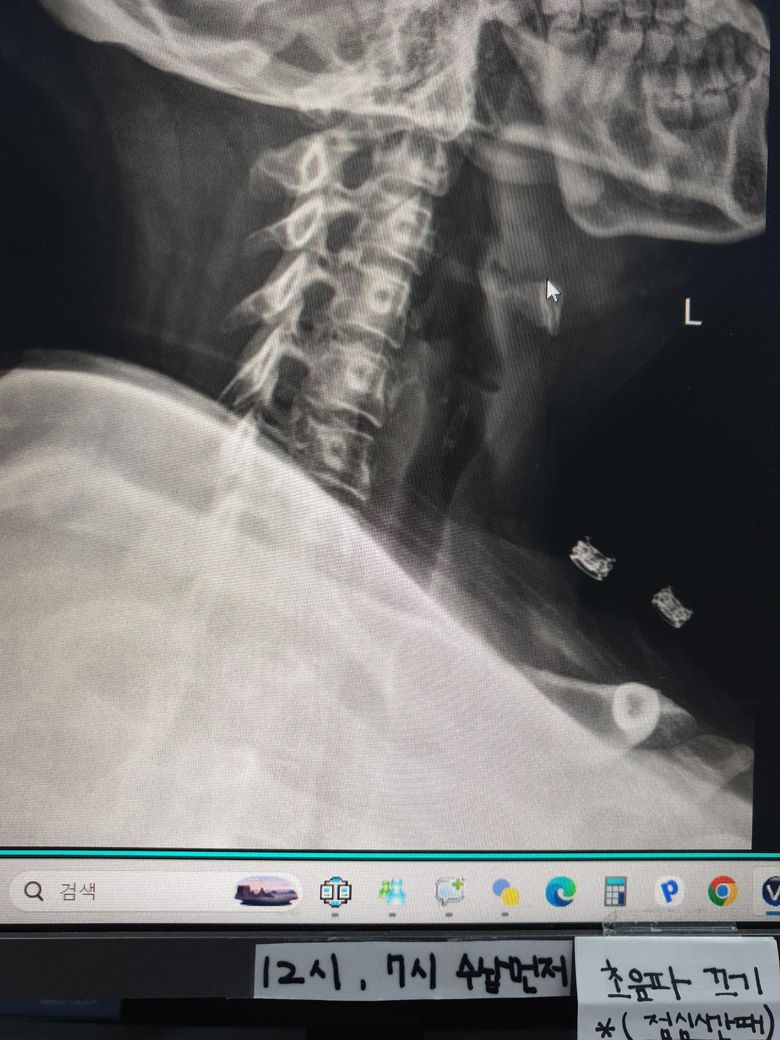

• 3번 째 사진

x-ray 상으로 보았을 때에는 일자목인 것으로 보입니다.

사진상으로 많은걸확인할수는없지만 일자목과함께 약간의 거북목을 가지고있는걸로 보이는데요 이는 굽은등과 평소 자세적인문제등에 의해서 나타날수있습니다~

엑스레이 사진을 보니 일자목 경향이 보이며 이로인해 목 뒤쪽 근육과 후두신경이 계속 긴장해 통증이 발생하는것으로 보입니다. 옆으로 누워 주무시는에 어깨가 말려있다면 어깨 높이를 충분히 받쳐주어 목이 아래로 꺾이지 않도록 유도하는 베개가 필수입니다. 4만원대 예산이라면 메모리폼이나 엘라스틱 소재의 경추형 베개중에서도 양옆이 가운데보다 높은 디자인이 좋습니다. 너무 말랑한것보다는 탄성이 있는 제품이 신경눌림 방지에더 효과적이며, 수건을 말아 목뒤에 받쳐보며 본인에게 맞는 높이를 먼저 테스트해보는것이 좋습니다. 답변이도움됐길 바랍니다!

• 제시된 측면 경추 X-ray를 보면 정상적으로 유지되어야 할 경추 전만(앞쪽으로 휘는 곡선)이 다소 감소되어 보입니다. 이런 경우 후경부 근육 긴장과 후두부 방사통, 말씀하신 신경이 뻗치는 느낌이 흔히 동반됩니다. 베개 선택이 증상에 직접적인 영향을 줄 수 있는 상태입니다.

핵심은 “높은 베개”가 아니라 “경추를 받쳐주는 구조”입니다. 현재처럼 어깨가 말리고 옆으로 주로 주무시는 경우라면 단순히 낮은 베개는 오히려 기도를 좁히고 근육 긴장을 악화시킬 수 있습니다.

옆으로 잘 때 기준으로는 어깨 두께를 채워서 머리와 척추가 일직선이 되도록 해야 합니다. 일반적으로 성인 여성 기준 압축 후 높이가 약 8에서 12cm 범위가 적절한 경우가 많습니다. 다만 중요한 것은 중앙이 꺼지는 형태가 아니라, 목을 받치는 부분이 살짝 더 높은 “경추 지지형” 구조입니다. 메모리폼이 무난하며 너무 푹 꺼지는 제품은 피하는 것이 좋습니다.

뒤로 누웠을 때 기준으로는 목 아래를 받쳐주고 머리는 약간 낮게 위치하는 형태가 이상적입니다. 즉, C자 형태로 경추를 지지해주는 베개가 적합합니다. 이런 구조가 없으면 현재처럼 후두부 통증이 지속될 수 있습니다.

정리하면, 옆으로 잘 때는 어깨 높이를 채우는 충분한 높이, 동시에 목을 따로 지지하는 경추 지지 구조, 너무 부드럽지 않은 소재가 기준입니다. 가격대 4만원이면 경추 지지형 메모리폼 제품 충분히 선택 가능합니다.

추가로, 통증이 가만히 있어도 지속되고 후두부에서 방사되는 양상이라면 단순 근육 문제 외에 후두신경통 가능성도 있습니다. 베개 교체 후에도 1주에서 2주 내 호전이 없으면 물리치료나 신경차단술 평가가 필요할 수 있습니다.